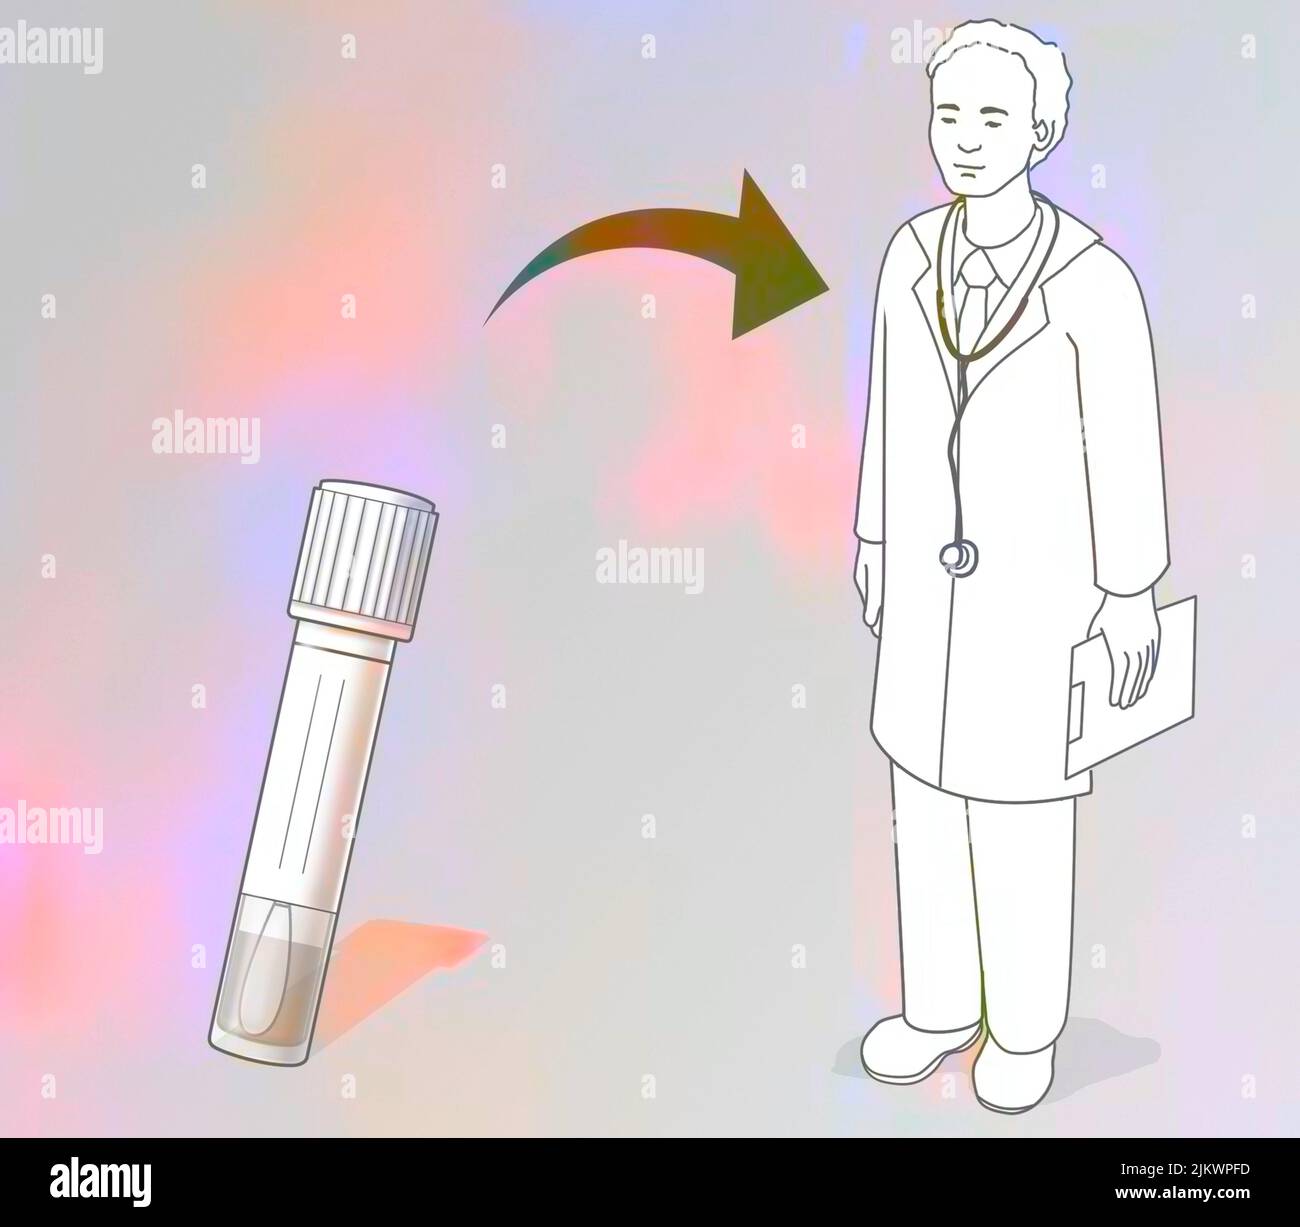

RF2JKWPFD–Auto-échantillonnage vaginal : l'écouvillon humide est administré au médecin pour analyse.